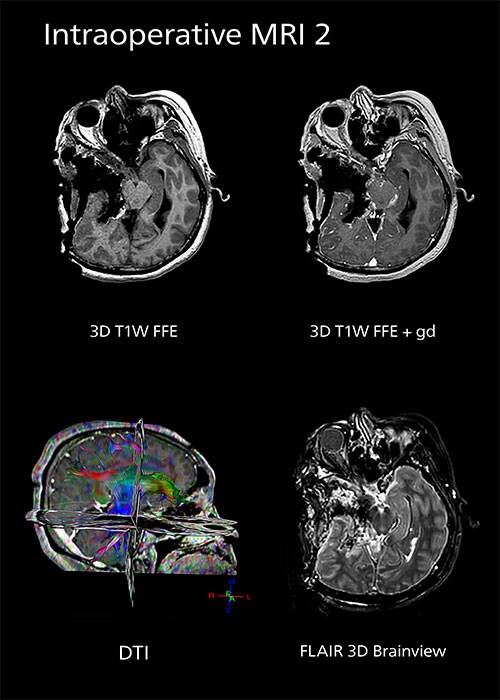

To enable evaluation of resection completeness or to acquire images to correct for brain shift, the MR staff will perform several sequences using a NORAS OR head coil (see Tokai ExamCard Table). Standard protocols for high-grade gliomas include:

| Sequence | Benefit | Resolution, C-SENSE factor, Typical scan time |

| Marker 3D T1W TFE | Marker visualization | 1.56 x 1.64 x 5 mm C-SENSE factor 3 0:31 min |

| 3D T1W TFE without and with gadolinium (Gd) enhancement | Contrast-enhanced T1 is useful because high grade gliomas are typically Gd-enhanced. | 1.03 x 1.08 x 1.20 mm C-SENSE factor 3.5 1:47 |

| 3D FLAIR BrainView | For non-enhancing gliomas. Helps in identifying low-grade glioma and for distinguishing brain edema from tumor. | 1.1 x 1.1 x 2.4 mm C-SENSE factor 5 5:01 min |

| Diffusion tensor imaging (DTI) | Visualization of the anatomical location of white matter tracts. Fiber tracking software converts these images to a parametric color-coded display of white matter fiber tracts. In tumor resection surgery, it is critical to know the topographic relation of white matter fiber tracts (e.g., associated with Broca’s or Wernicke’s functional areas) that are near a lesion and the connecting fibers originating from these regions. | 3 mm isotropic 3:14 min |

| Diffusion-weighted (DWI) | Evaluation of ischemic complications (e.g., stroke). | 1.9 x 1.9 x 5.0 mm 0:45 min |